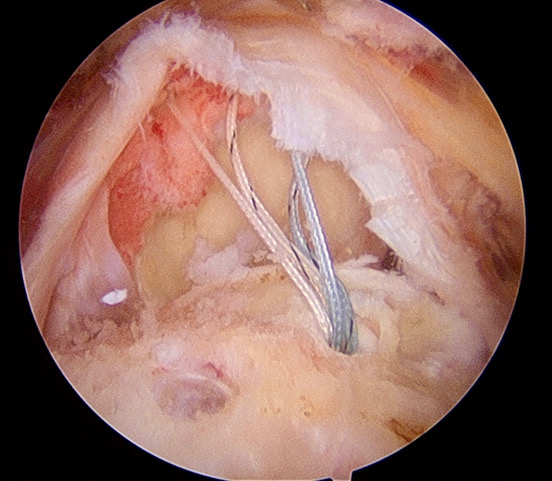

En ciertos casos, una operación puede ser la mejor opción para solucionar los síntomas. Habitualmente se realiza por artroscopia, una cirugía poco invasiva en la que, a través de pequeñas incisiones en la piel se introducen una cámara y diferentes instrumentos para realizar los gestos que se crean convenientes. Es importante que el cirujano que lo vaya a realizar tenga una amplia experiencia en este tipo de cirugías para conseguir los mejores resultados posibles.